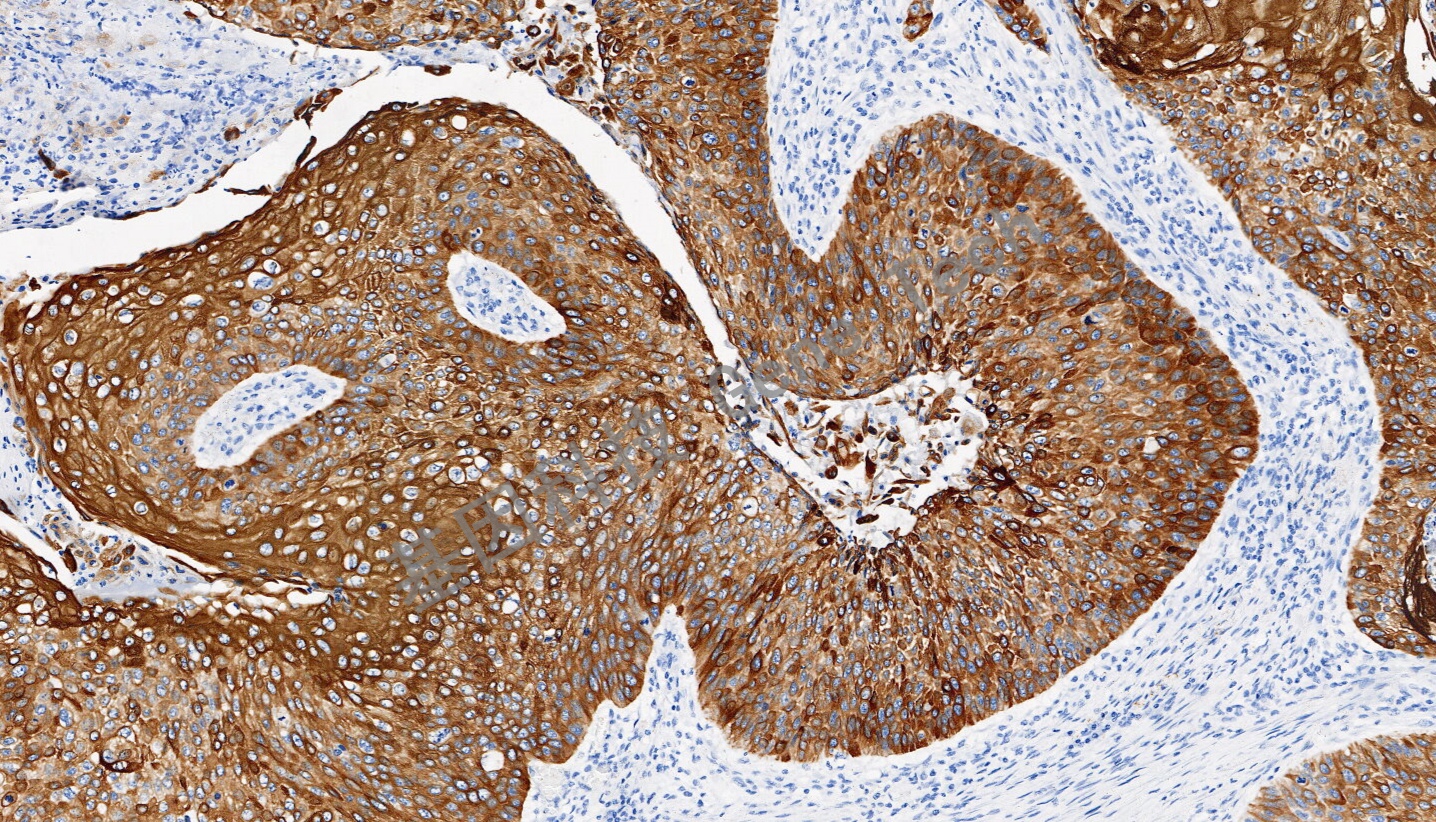

| 簡介:細胞角蛋白6(CK6)是一種上皮特異性的II型角蛋白,通常與創傷后的角質細胞活化相關,因此也被認為是一類愈合因子。CK6總是與I型角蛋白CK16和/或CK17成對出現,通常在尚未角質化的上皮組織的基底層細胞中表達,如口腔粘膜、食道、舌乳頭,在毛囊外根鞘中也有明顯表達。在腫瘤組織中,CK6在多數的鱗狀上皮癌中表達,特別是在鱗癌癌巢的中間成熟細胞層。CK6通常與CK5一起配套用于鱗癌與腺癌、間皮瘤與腺癌的鑒別診斷,也可用于導管上皮惡性增生的鑒別。 | ||

| 食道癌石蠟切片,用 CK6(GT2490)染色,細胞漿陽性,DAB 顯色。 | ||